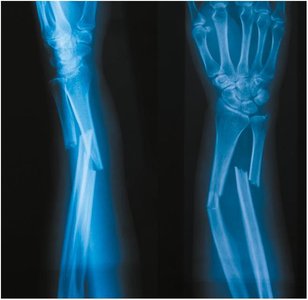

Types of Fractures

Fractures are classified by the pattern and cause of the break:

• Colles fracture: Distal radius broken by falling on an outstretched hand.

X-ray of a forearm fracture involving radius and ulna Colles fracture illustration Comminuted fracture illustration Compression fracture illustration Depressed fracture illustration Greenstick fracture illustration Hairline fracture illustration Oblique fracture illustration Transverse fracture illustration